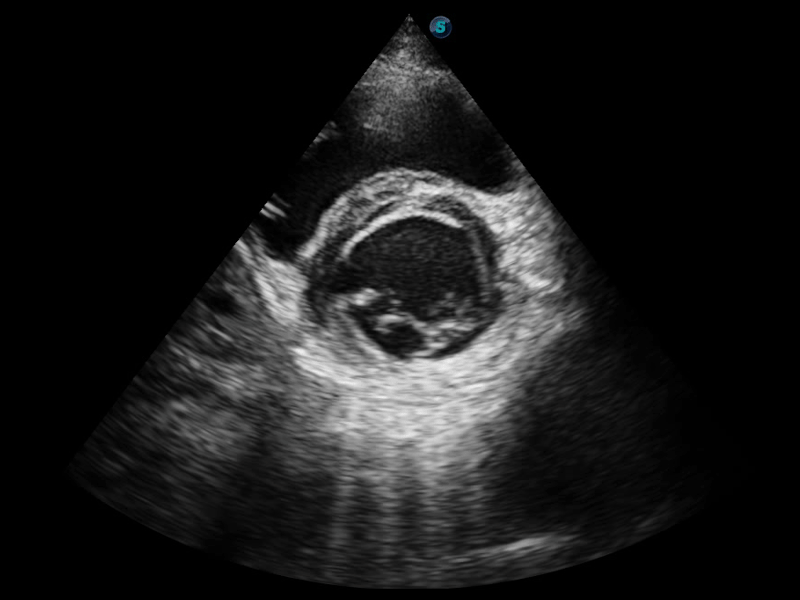

组织多普勒

组织多普勒成像功能,可提供心肌运动速度和其他临床信息,使临床医生能够分析和比较患者心脏不同部位的运动。